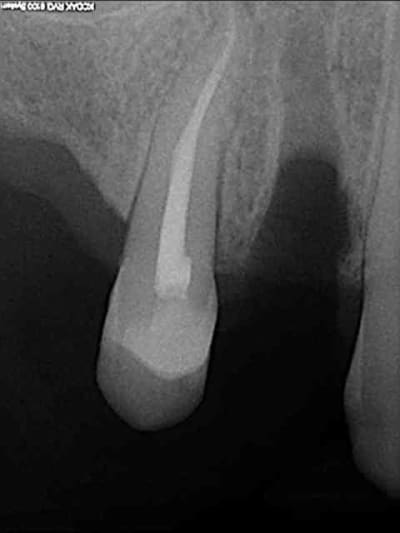

18/10/2011 à 11h19

Céramik écrivait:

-----------------

> Jolie, tu as un radio post-op ?

aussitôt demandé, aussitôt fait !!

(j+1 an)

tu as perdu pas mal d'os!!